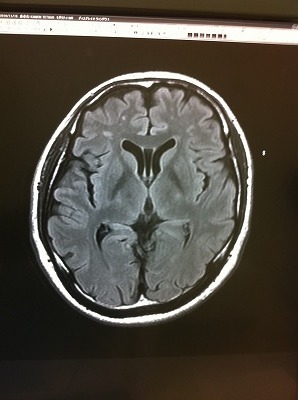

で、先生が、この写真を見ながら、、

「ちょっと気になる点があるんですよね。。。。」

「やっぱり、、、なにもないはずがない。。。」

「写真で言う所の、左上に、白い島のようなものが見えますよね。。。」

確かに、、ありますね。。。

「その部分は、脳が死んでいる所です」 「小梗塞、もしくはラクナ梗塞といいます」

※ラクナ梗塞(小梗塞)

脳の細い血管が詰まって起こる脳梗塞

脳に入った太い血管は、次第に細い血管へと枝分かれしていきます。ラクナ梗塞はこの細かい血管が高血圧による血管変性や動脈硬化が原因で狭くなり、詰まることによって起きます。脳の血管の閉塞により、脳の組織の一部が死んで脱落し空洞を残すためにラクナ(小さなくぼみ)梗塞と呼ばれています。日本人に最も多いタイプの脳梗塞です。

※症状

小さな脳梗塞ですが運動障害や感覚障害、言語障害を起こすことがあります。こうした場合は通常の脳梗塞と同じような治療が必要になります。

また症状がはっきりしない場合は無症候性と言いますが、再発により神経症状が出現する率が高くなってしまうのと、再発を繰り返すことで認知症の原因になってしまうのでラクナ梗塞の再発を予防(高血圧、糖尿病、高脂血症といった動脈硬化の危険因子の改善)していくことが、治療の方法となります。

ん。。。。。「今すぐ治療の必要はないですが、煙草や食生活には充分注意してください。」 はい。。

「死んでいますから、改善はしません。進行を止める。遅らせる事は出来ます」

「60歳を過ぎると、この程度は普通です。ちょっと早いね。」